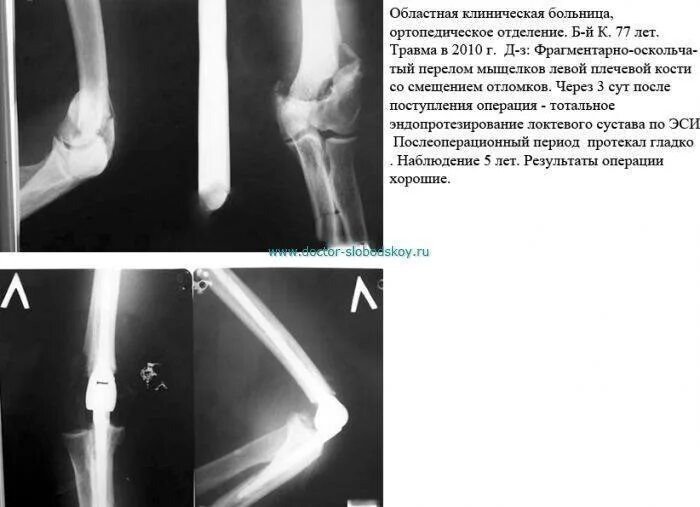

Оскольчатый перелом со смещением